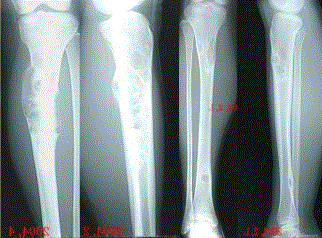

问题 患者女,20岁,右小腿疼痛1周。行双小腿正侧位CR,并行双小腿CT及MR扫描,见下图。 对于此病变的征象,描述不正确的是

选项 A.双侧胫骨骨干不规则膨胀性溶骨破坏 B.病灶边缘清楚,可见硬化缘 C.病灶呈磨砂玻璃样密度 D.在T1WI与T2WI上均表现为低信号,提示为纤维组织 E.病灶内可见多发囊状长T1,长T2信号影,为液化坏死区,提示病变为恶性病变

答案 E